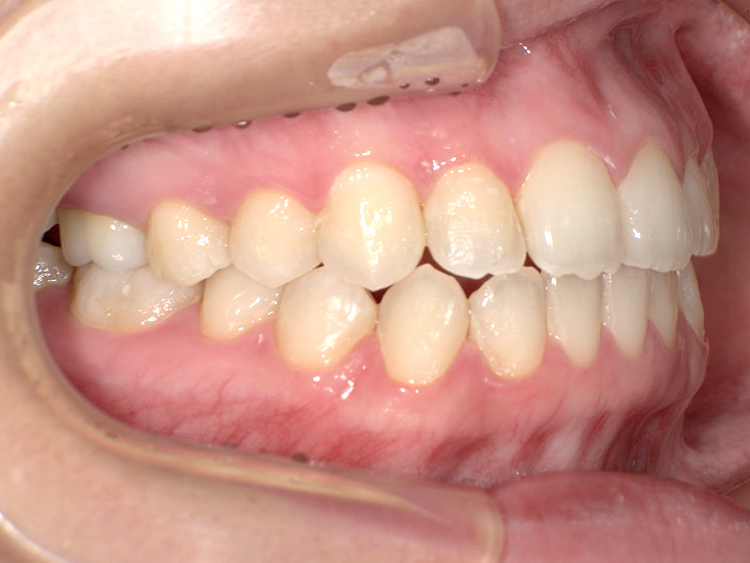

症例5

Before

After

| 主訴 | 上下3-3の並びが気になる |

|---|---|

| 年齢 | --- |

| 治療 期間 |

約1年 |

| 治療 内容 |

インビザライン5-5 |

| 治療費 | ¥517,000(税込)/調整料含む |

| 治療のリスク | 奥歯を動かさないので、前に出して並べていく。 歯と歯が移動するスペースを作るので、知覚過敏の症状がまれにでる。 歯を動かすことで、歯茎が下がるリスクある。 矯正終了後は、リテーナーを使用し、後戻りを防ぐ必要がある。 |